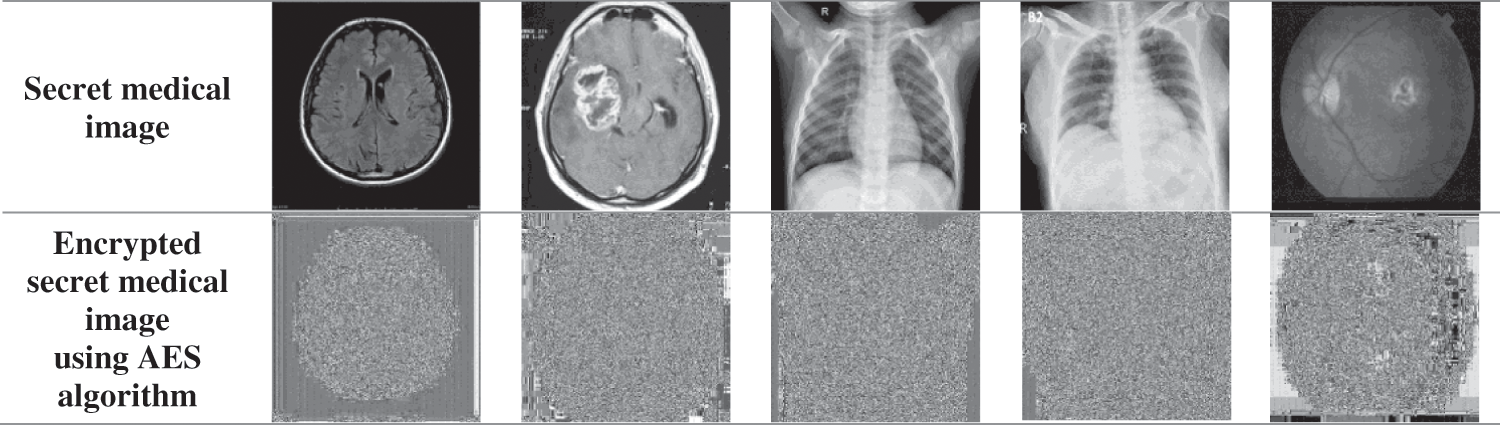

The most important step in this technique is the first step, which is the encryption of the secret medical image to be transmitted, securely. The AES algorithm does the encryption and decryption processes. AES encryption is done in rounds, where we process 16 pixels in each round. The results of image encryption are shown in Fig. 7.

Figure 7: Encrypted secret medical image using AES algorithm